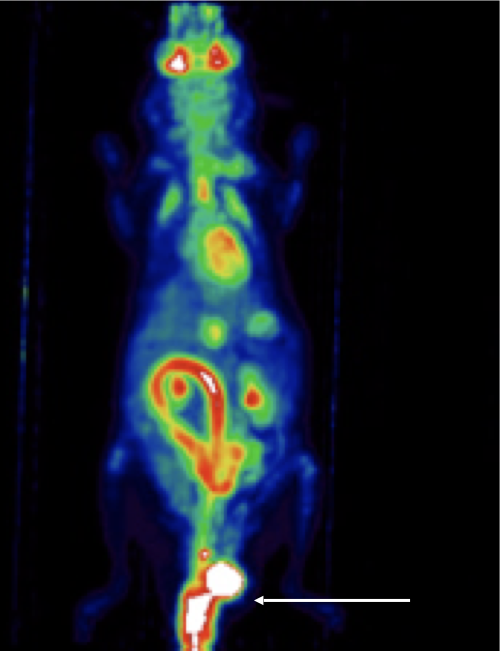

CASE 3: Mouse PET imaging of colorectal cancer

Research objective:PET imaging to detect colorectal cancer and possible metastasis in a specific knocked-out mouse model. Arrows show the lesion in mice of the KO group.

Animal model:Mouse, 20-25g

Acquisition protocol:10 min acquisition time, 1 bed position

Processing and reconstruction protocol:3D-OSEM, 0.42 x 0.42 x 0.855 voxel size

Biomarker or contrast agent:Mice were injected with ~10 MBq [18F]FDG in jugular vein (i.v.). Imaging at 1 h post injection.